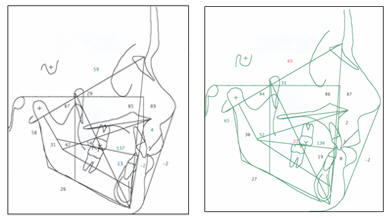

CEFALOGRAMAS DEL PACIENTE: Ricketts - Jarabak |

Fig.

5.- Cefalograma del paciente según Ricketts y Jarabak. |

Las medidas

cefalométricas revelaron un ángulo SNA de 83º, un SNB de 77.8 y un

ANB de 5.2º, el ángulo interincisivo tiene 137º, y el incisivo

inferior en relación a APg. Esta a -2 mm, la Base Craneal Posterior

muy grande 41 mm. (fig. 5 y en cefalogramas presentados al final de

esta descripción, antes y al final del tratamiento)

Telerradiografía antes y al final del tratamiento (Fig.

# 23) |

Fig.#

23.-En las telerradiografías antes y al final del

tratamiento podemos destacar especialmente la reducción

del overjet, de tal manera que se ha obtenido una buena

relación entre dentadura superior e inferior, nótese

además la migrasión a mesial de los sectores posteriores

superiores, de tal manera que va a ser necesario

mantenerse a los terceros molares superiores a fin de

que ocluyan con los segundos inferiores. |

Los trazos

cefalométrico antes y después del tratamiento como sus

correspondientes valores degún Ricketts, Jarabak y McNamara se

presentan a continuación de manera integral.

|

1 DE

JULIO DEL 1996 |

23 DE

ABRIL - 2002 |

|

|

RICKETTS |

| |